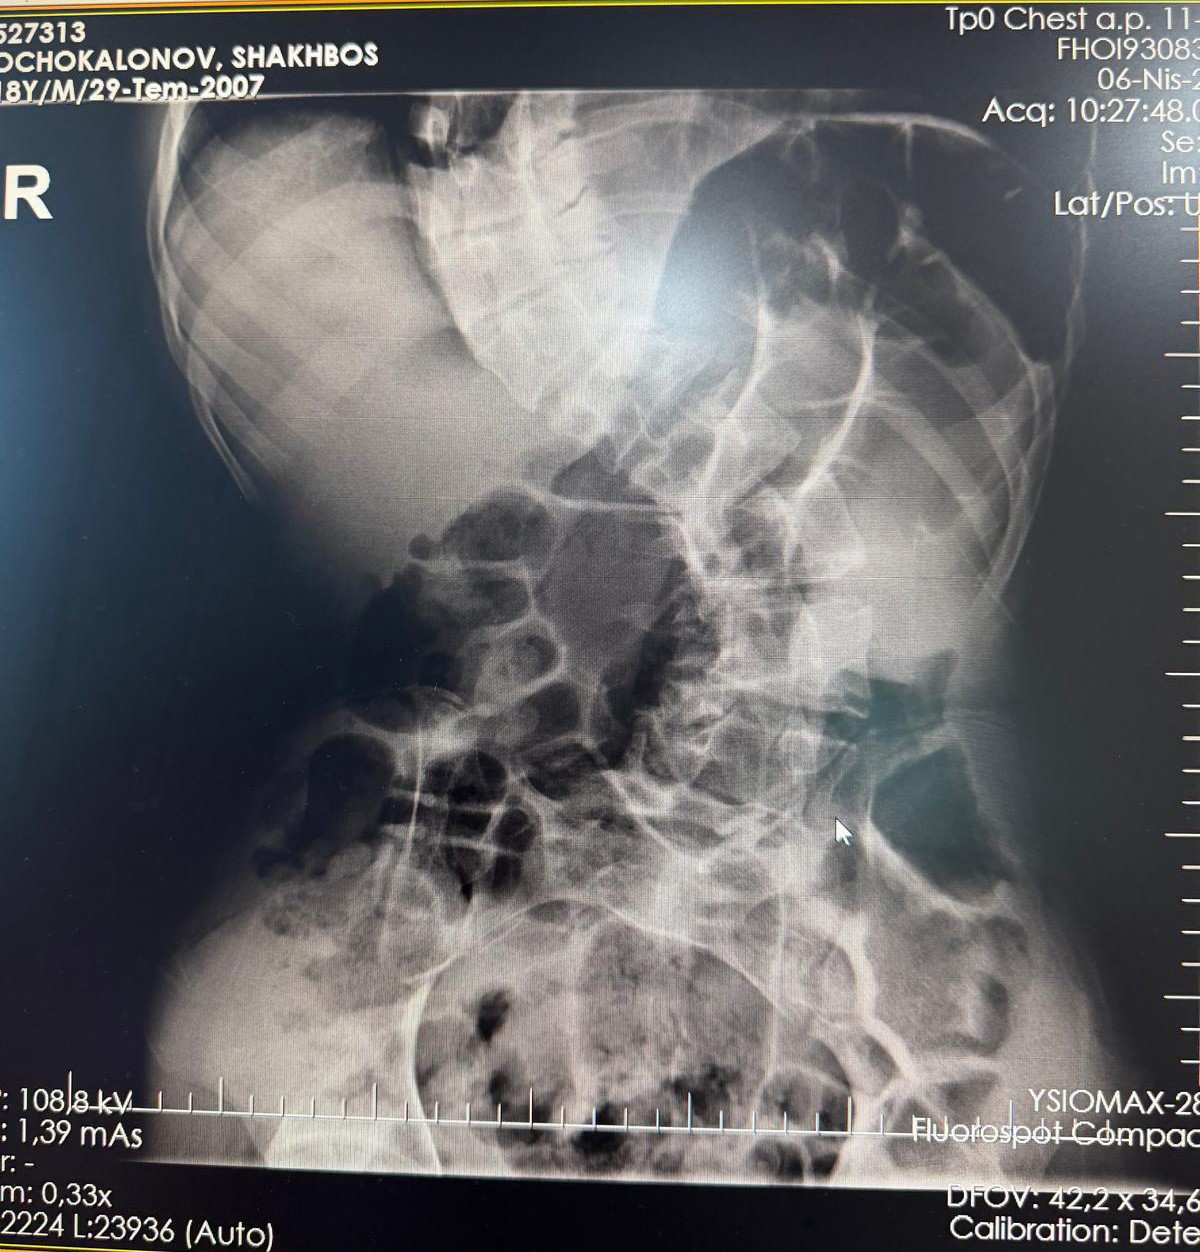

Başarılı geçen ameliyat sonrası hastanın yaşam kalitesinin önemli ölçüde arttığını belirten Ortopedi ve Travmatoloji uzmanı Prof. Dr. Mehmet Atıf Erol Aksekili, skolyoz hakkında bilgi vererek, "Skolyoz kısaca omurganın S şeklini almasıdır. Ön-arka planda omurganın S şeklini almasını biz kısaca skolyoz diyoruz. Skolyoz en sık adolesan dediğimiz ergenlik döneminde görülür. Ancak diğer hastalıklarla birlikte görüldüğünde daha ileri seviyelerde karşımıza çıkabilir. Hastamız 18 yaşında bize başvurdu. Nöromüsküler skolyoz dediğimiz, nörolojik hastalıkların eşlik ettiği bir skolyoz tipi mevcut. Bu skolyozlar erken yaşta ortaya çıkar ve daha hızlı ilerler. Bu yüzden hastamız bize 90 dereceden daha ileri bir seviyede başvurdu" dedi.

Erken teşhis edilmesi halinde daha az cerrahi ile daha iyi sonuç alınabileceğini belirten Aksekili, "Skolyoz erken tanındığında fizik tedavi, egzersiz ve korseleme gibi yöntemlerle ilerlemesini kontrol altına alabiliyoruz. Hastamızda ileri skolyoz olduğu için iki aşamalı cerrahi uygulandı. İlk aşamada Halo Femoral traksiyon yöntemiyle skolyoz kısmen düzeltildi. İkinci aşamada ise vidalar, rodlar ve osteotomi ile omurga düzeltildi" diye konuştu.